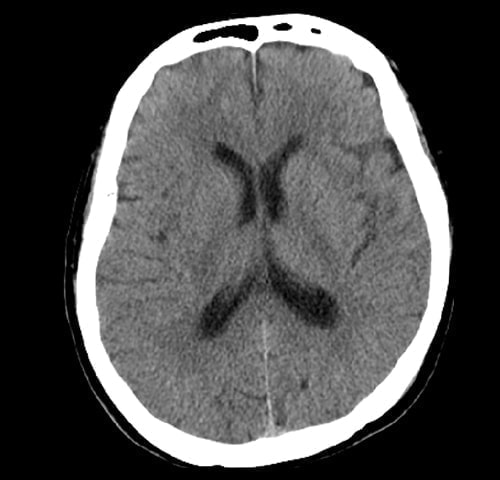

(脳出血・脳梗塞・脳腫瘤)病変

脳